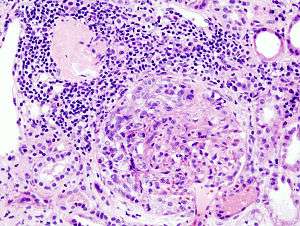

| Histopathological image of crescentic glomerulonephritis in a patient with MPO-ANCA positive rapid progressive glomerulonephritis. Hematoxylin & eosin stain. | |

Rapidly progressive glomerulonephritis (RPGN) is a syndrome of the kidney that is characterized by a rapid loss of renal function,[1][2] (usually a 50% decline in the glomerular filtration rate (GFR) within 3 months)[2] with glomerular crescent formation seen in at least 50%[2] or 75%[1] of glomeruli seen on kidney biopsies. If left untreated, it rapidly progresses into acute renal failure[3] and death within months. In 50% of cases, RPGN is associated with an underlying disease such as Goodpasture syndrome, systemic lupus erythematosus or granulomatosis with polyangiitis; the remaining cases are idiopathic. Regardless of the underlying cause, RPGN involves severe injury to the kidneys' glomeruli, with many of the glomeruli containing characteristic glomerular crescents (crescent-shaped scars).